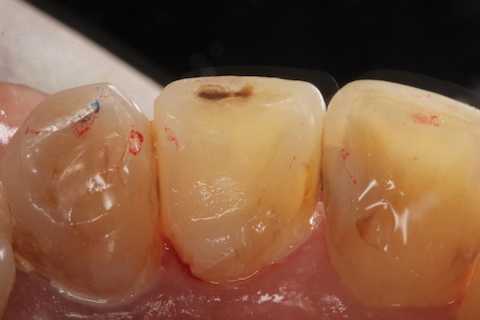

とりあえず健全歯質を確保して、露髄部分は直覆してCRで再建した。

では時系列で、どうぞ